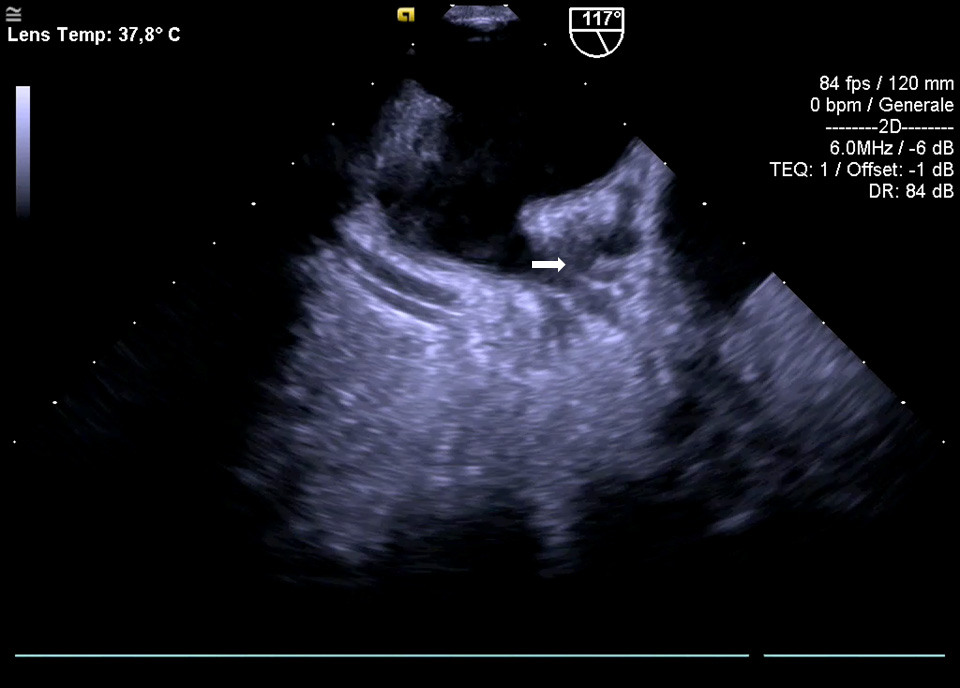

The main TOE e/o CCTA exclusion criterion is the existence of thrombus in the LAA [35]. Nowadays, TOE is the most used imaging technique to exclude the presence of thrombi in LAA (Fig. 3).

Fig. 3.The main TOE e/o CCTA exclusion criterion is the existence of thrombus in the LAA (see arrow).